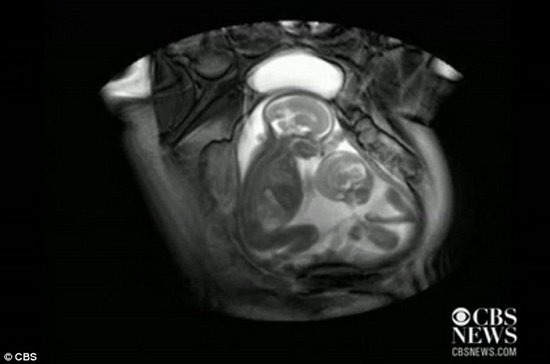

最新磁共振图像显示双胞胎在母体腹中拳脚相加争夺“地盘”

腾讯科学讯(悠悠/编译) 据英国每日邮报报道,双胞胎从小到大都喜欢在一起拌嘴,这已是司空见惯的事情了。但人们或许没想到双胞胎出生之前在母亲身体中就存在着“争斗”。英国伦敦帝国理工学院专业化磁共振成像扫描仪拍摄视频显示一对双胞胎在母亲子宫中彼此踢腿。

图像右侧的较小胎儿正在踢较大的胎儿,他试图争取更多的空间。最初较大的胎儿并不在意,但最终意识到较小的胎儿正在用膝盖顶自己并进行了还击。整个过程被磁成磁共振成像扫描仪记录了下来。这对双胞胎已有20个星期,研究过程并不知道胎儿的性别和母亲的身份。

此次磁共振成像扫描仪成像研究是用于监控分析双胎输血综合症(TTTS),该状态下双胞胎儿共享一个胎盘,因此具有相同的血液供给。一个胎儿获得较多的血液,这将导致高血压和尽力衰竭,而另一个胎儿则不会获得足够的血液供给。如果未进行及时治疗处理,90%胎儿将死亡,存活下来的胎儿很可能将患有肾衰竭或者脑性瘫痪。

玛丽莎-泰勒-克拉克博士使用这种扫描来监控24对双胎输血综合症胎儿,她说:“通过磁共振成像扫描仪,能够让我们观测到胎儿在母体中的空间多大,他们以何种方式推挤另一个胎儿。”

这种扫描也被称为“默剧-核磁共振”,能够比超声波建立更多的图像,但是玛丽莎称,该扫描方法将不会用于常规性孕检,有时我们会发现无法解释的状况,一些情况可能是由于孕妇过度紧张所致。